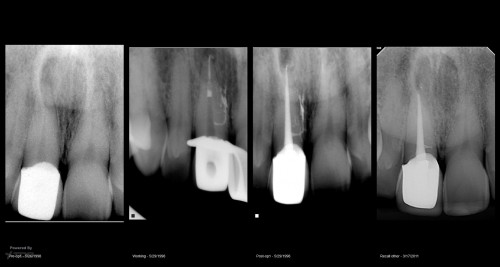

#19 Caries Driven access

By Reuben Joseph / July 17, 2018

Clinical Scenario and treatment done DO caries with a deep sub-gingival margin Resorbed apex – […]

#30 – Caries Driven Access

By Reuben Joseph / July 16, 2018

#30 Pulpitis. Caries involving the ML cusp. Caries driven access planned   Mb located in the middle […]